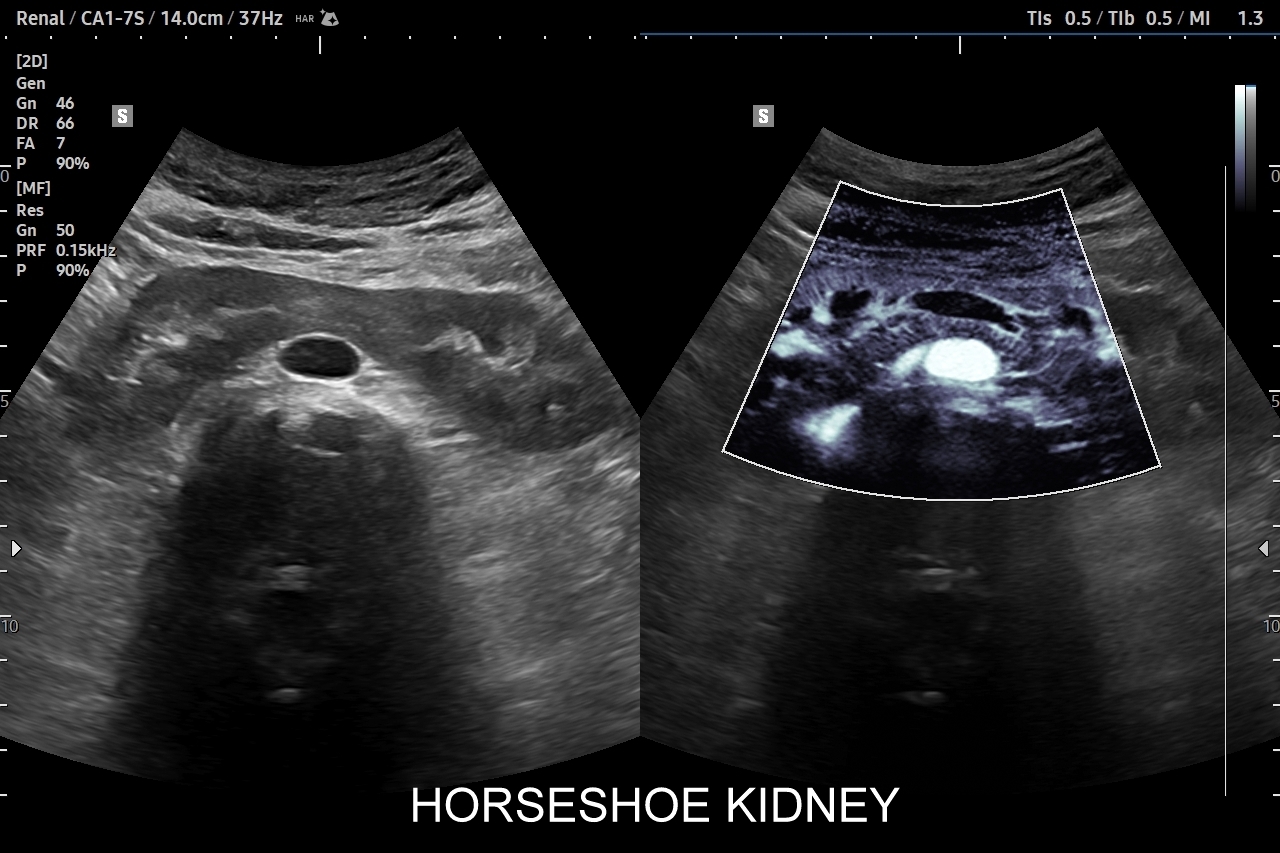

Doppler przepływów nerkowych (USG przepływy nerkowe) jest połączeniem badania obrazowego USG z badaniem funkcjonalnym nerki, jej naczyń tętniczych i żylnych oraz globalnie stanu układu krążenia. Najczęstszym wskazaniem do wykonania USG Doppler tętnic nerkowych, będącego częścią USG Doppler przepływów nerkowych, jest nadciśnienie tętnicze i poszukiwanie jego przyczyn w postaci zwężenia tętnic nerkowych, które mogą wystąpić w odcinku przednerkowym, jak i wewnątrznerkowym. Wykonanie oceny dopplerowskiej nerki jest szczególnie ważne w przypadku wystąpienia nadciśnienia tętniczego u osób młodych lub u dzieci.

Inne wskazania do przeprowadzenia diagnostyki USG przepływów nerkowych obejmują ocenę funkcji nerek w przebiegu chorób ostrych oraz przewlekłych, takich jak nefropatia cukrzycowa, glomerulopatie, czy zapalenia kłębuszków nerkowych. Badanie USG Doppler wykonywane jest również przy podejrzeniu zakrzepicy żyły nerkowej i zespołu „dziadka do orzechów”; przy stwierdzeniu obecności żylaków powrózka nasiennego u mężczyzn; żylaków miednicy u kobiet; w sytuacjach, gdy podczas standardowego badania USG jamy brzusznej uwidoczniono patologię nerki (np. guz nerki, marskość); a także przy stwierdzeniu podwyższonych wartości parametrów nerkowych w badaniach laboratoryjnych (kreatynina, mocznik, cystatyna C, potas) oraz w ramach oceny USG nerki przeszczepionej.

W przypadku dostępu do nowoczesnej aparatury badanie USG Doppler przepływów nerkowych należy połączyć z obrazowaniem nerki w trybie mikrounaczynienia MVI / MVF, ewentualnie B-flow. Modalności te uzupełniają badanie dopplerowskie nerki i wnoszą dodatkowo ważne informacje, takie jak ocena aktywnej warstwy korowej nerki. Tryby mikrounaczynienia można również zastosować w diagnostyce różnicowej guzów oraz pseudoguzów nerki, co często pozwala na uniknięcie konieczności poddania się obciążającemu badaniu tomografią komputerową.